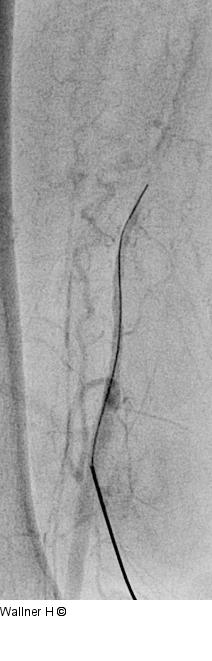

Abbildung 2a-c: Punktion - Arteria femoralis superficialis Erfolgreiche Punktion der distalen Art. femoralis superficialis rechts. |

Abbildung 2a

Abbildung 2b

Abbildung 2c

Abbildung 2a-c: Punktion - Arteria femoralis superficialis

Erfolgreiche Punktion der distalen Art. femoralis superficialis rechts. |